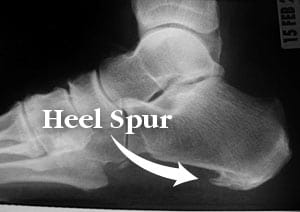

A heel spur is a bony protrusion that forms where the plantar fascia (a thick band of tissue running along the bottom of the foot) attaches to the heel bone. Heel spurs develop gradually over time due to repeated stress on the foot, which causes calcium deposits to accumulate in the affected area. Although many people with heel spurs don’t experience pain, others may feel sharp or aching pain, particularly when standing or walking.